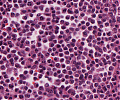

Multiples Myelom

Erkennbar sind dicht gepackte plasmazytoide Tumorzellen.